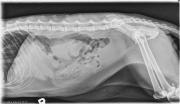

This week’s case is an 11-year-old male neutered domestic short haired cat. Presented for lethargy.

R LAT Abdomen

The liver is mildly enlarged, extending beyond the costal arch. The kidneys are enlarged with multifocal mineralization. The small intestine is mildly distended. On the ventrodorsal projection, there is a round, soft tissue opacity nodule between the craniolateral margin of the left kidney and the spleen. The bladder is large. A catheter is present in the left pelvic limb.

Diagnosis

A 1 cm mass was found in the distal left pancreatic lobe with abdominal ultrasound. This was biopsied as adenocarcinoma with intrapancreatic metastasis. Chronic renal failure was also diagnosed. No neoplasia was found in the liver or intestine.